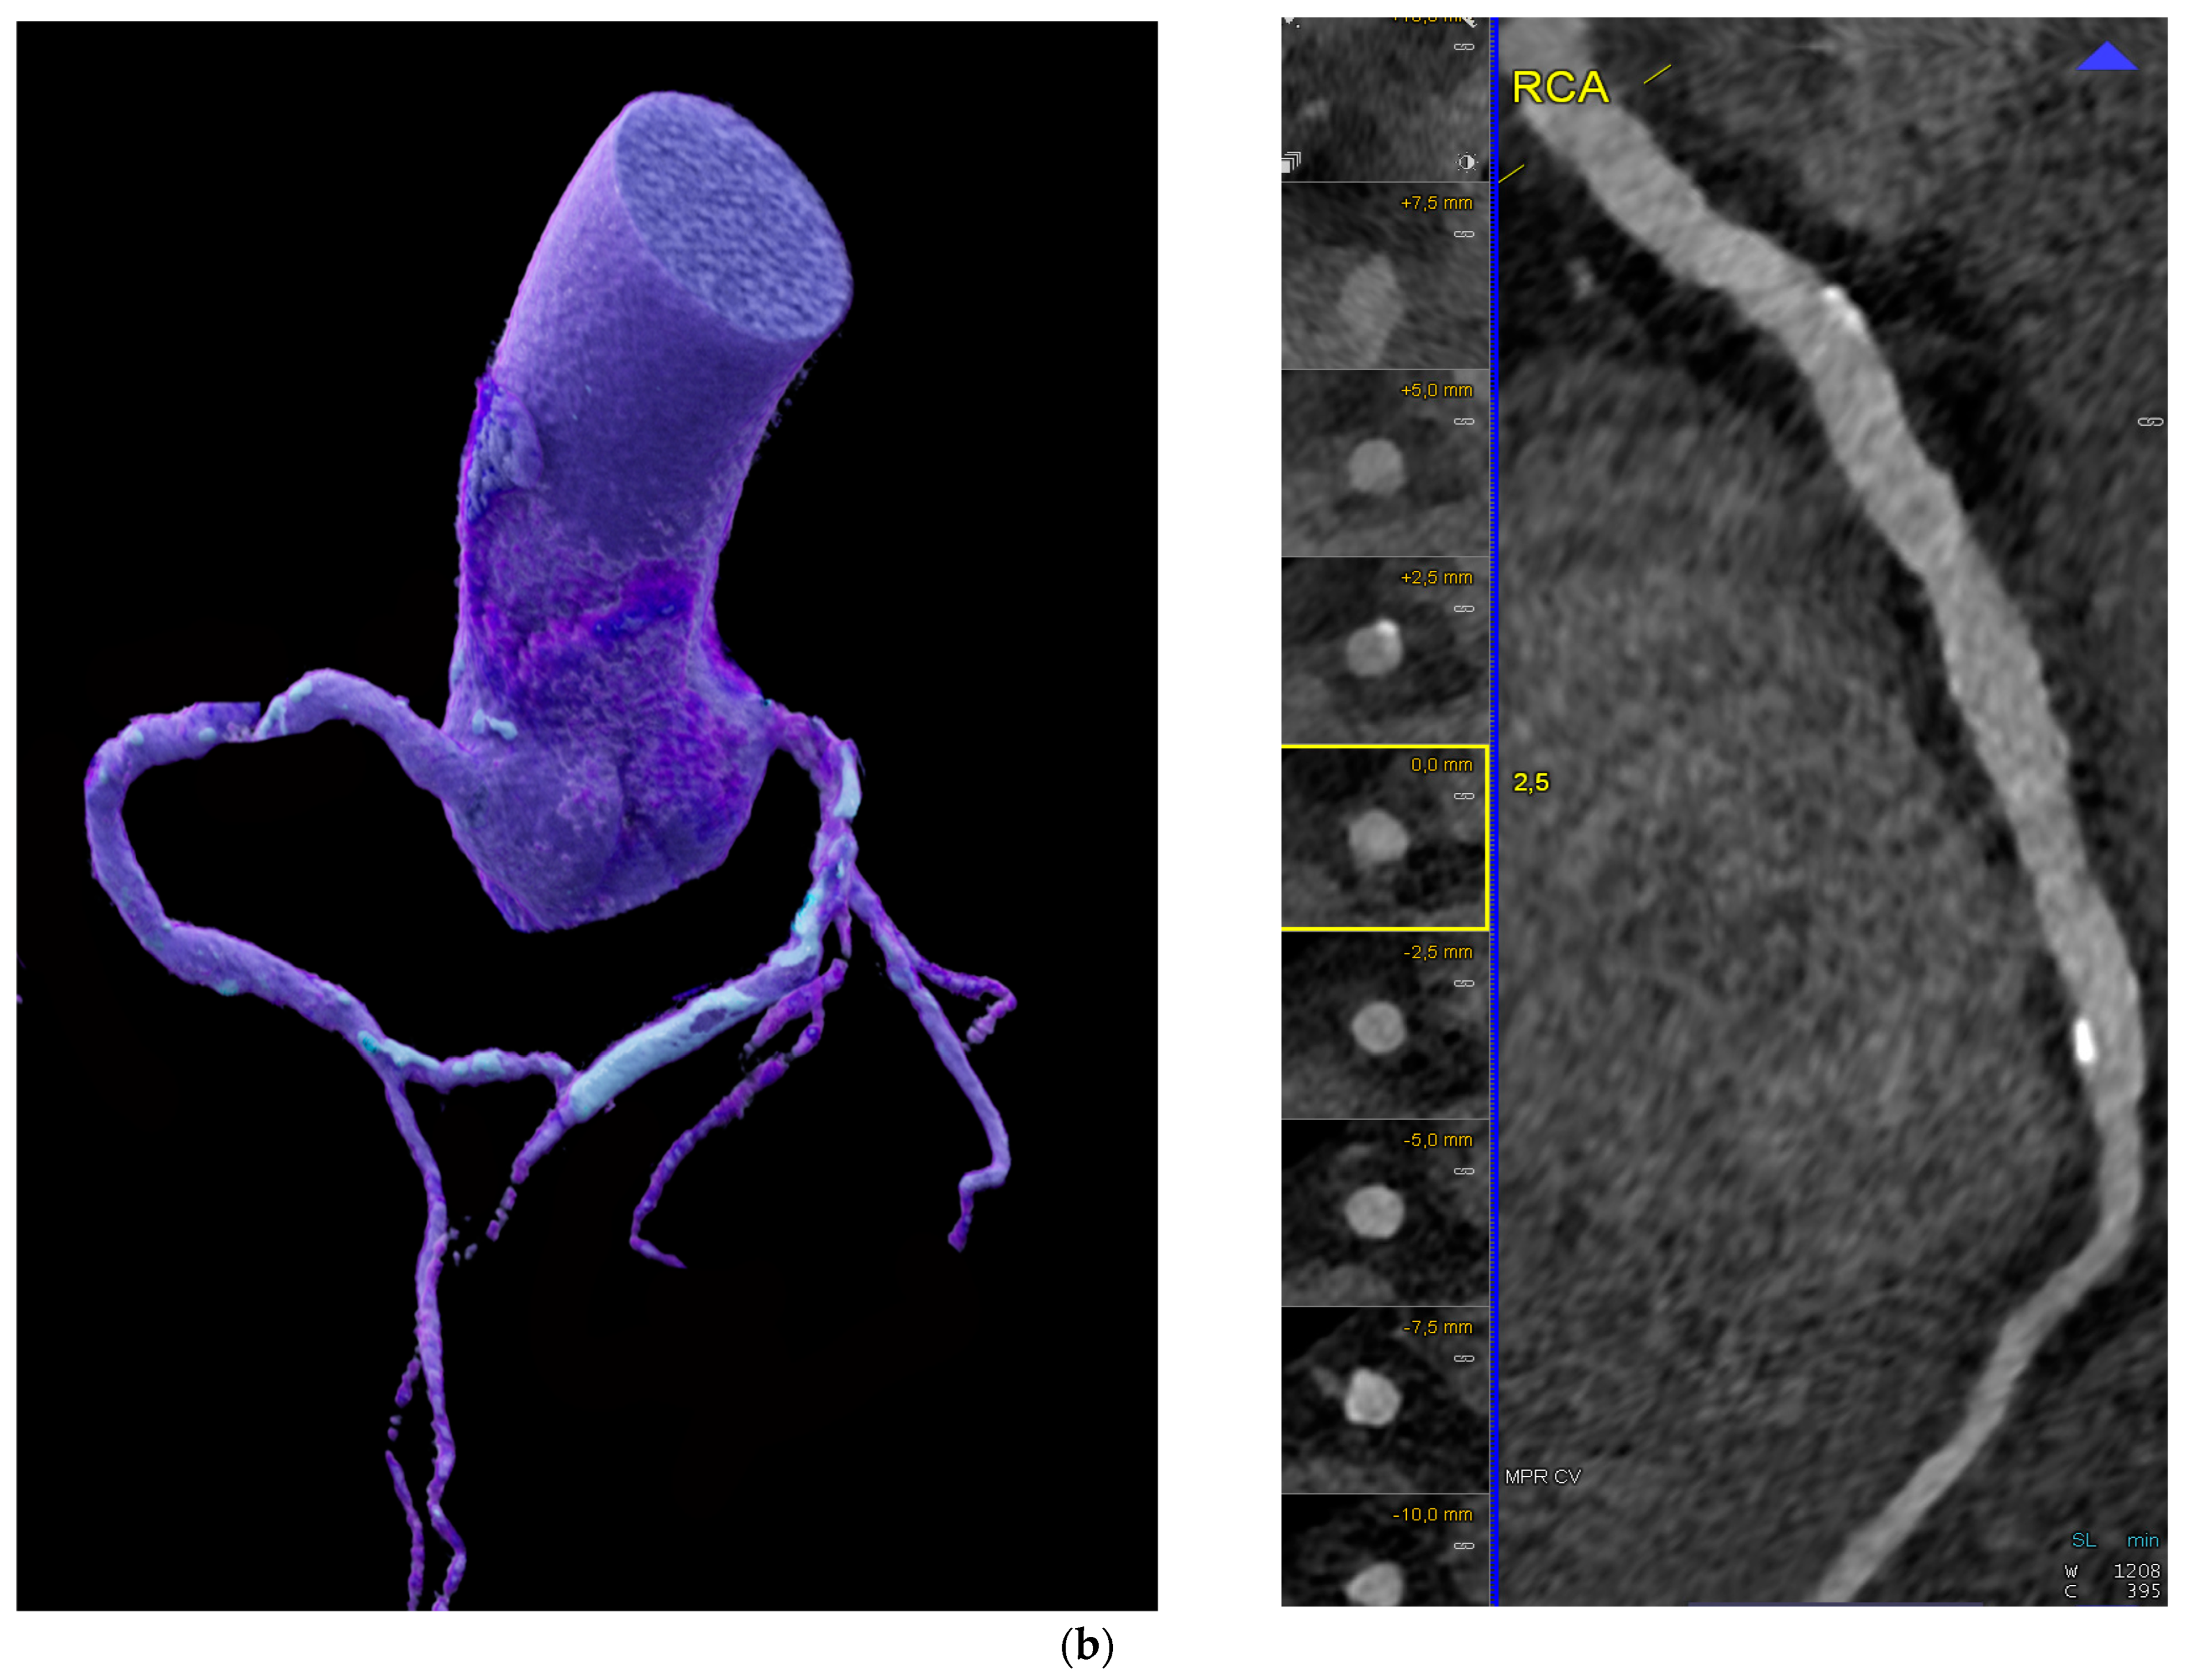

3.1. Does PCD-CT Have Potential to Reduce “Calcium Blooming” and Improve the Accuracy of Coronary Stenosis Grading?

| Accuracy of stenosis grading (UHR mode) | ||

| Koons et al. [21] | 23 patients 34 lesions | * Stenosis severity reduced in PCD-CT (p < 0.001): 11% reduction in percent diameter stenosis (%DS) * 15/34 underwent changes in stenosis severity |

| Halfmann et al. [22] | 114 patients (+in vitro phantom) | * Calcified lesions led to more accurate stenosis % * NCP and mixed equal |